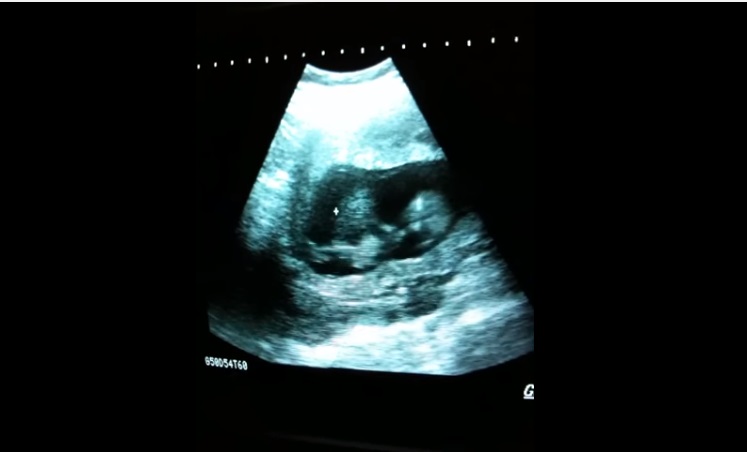

Les rendez-vous pour les échographies… ce sont tous des moments magiques vous ne trouvez pas ? On voit bébé à l’intérieur de notre bidou, on le voit grandir, on connaît ensuite son sexe si on ne souhaite pas avoir la surprise… Et ici, on peut dire que les futurs parents ont dû bien rire lors du rendez-vous chez le gynécologue. Les amies, avez-vous déjà vu pendant l’échographie (ou même senti) bébé jouer dans votre ventre ? Sur cette vidéo, on découvre un bout de chou qui prendre appui sur ses petites jambes et saute. Vous avez dit stupéfiant ?

Ce bébé a vraiment l’air de s’éclater dans le ventre de sa maman !